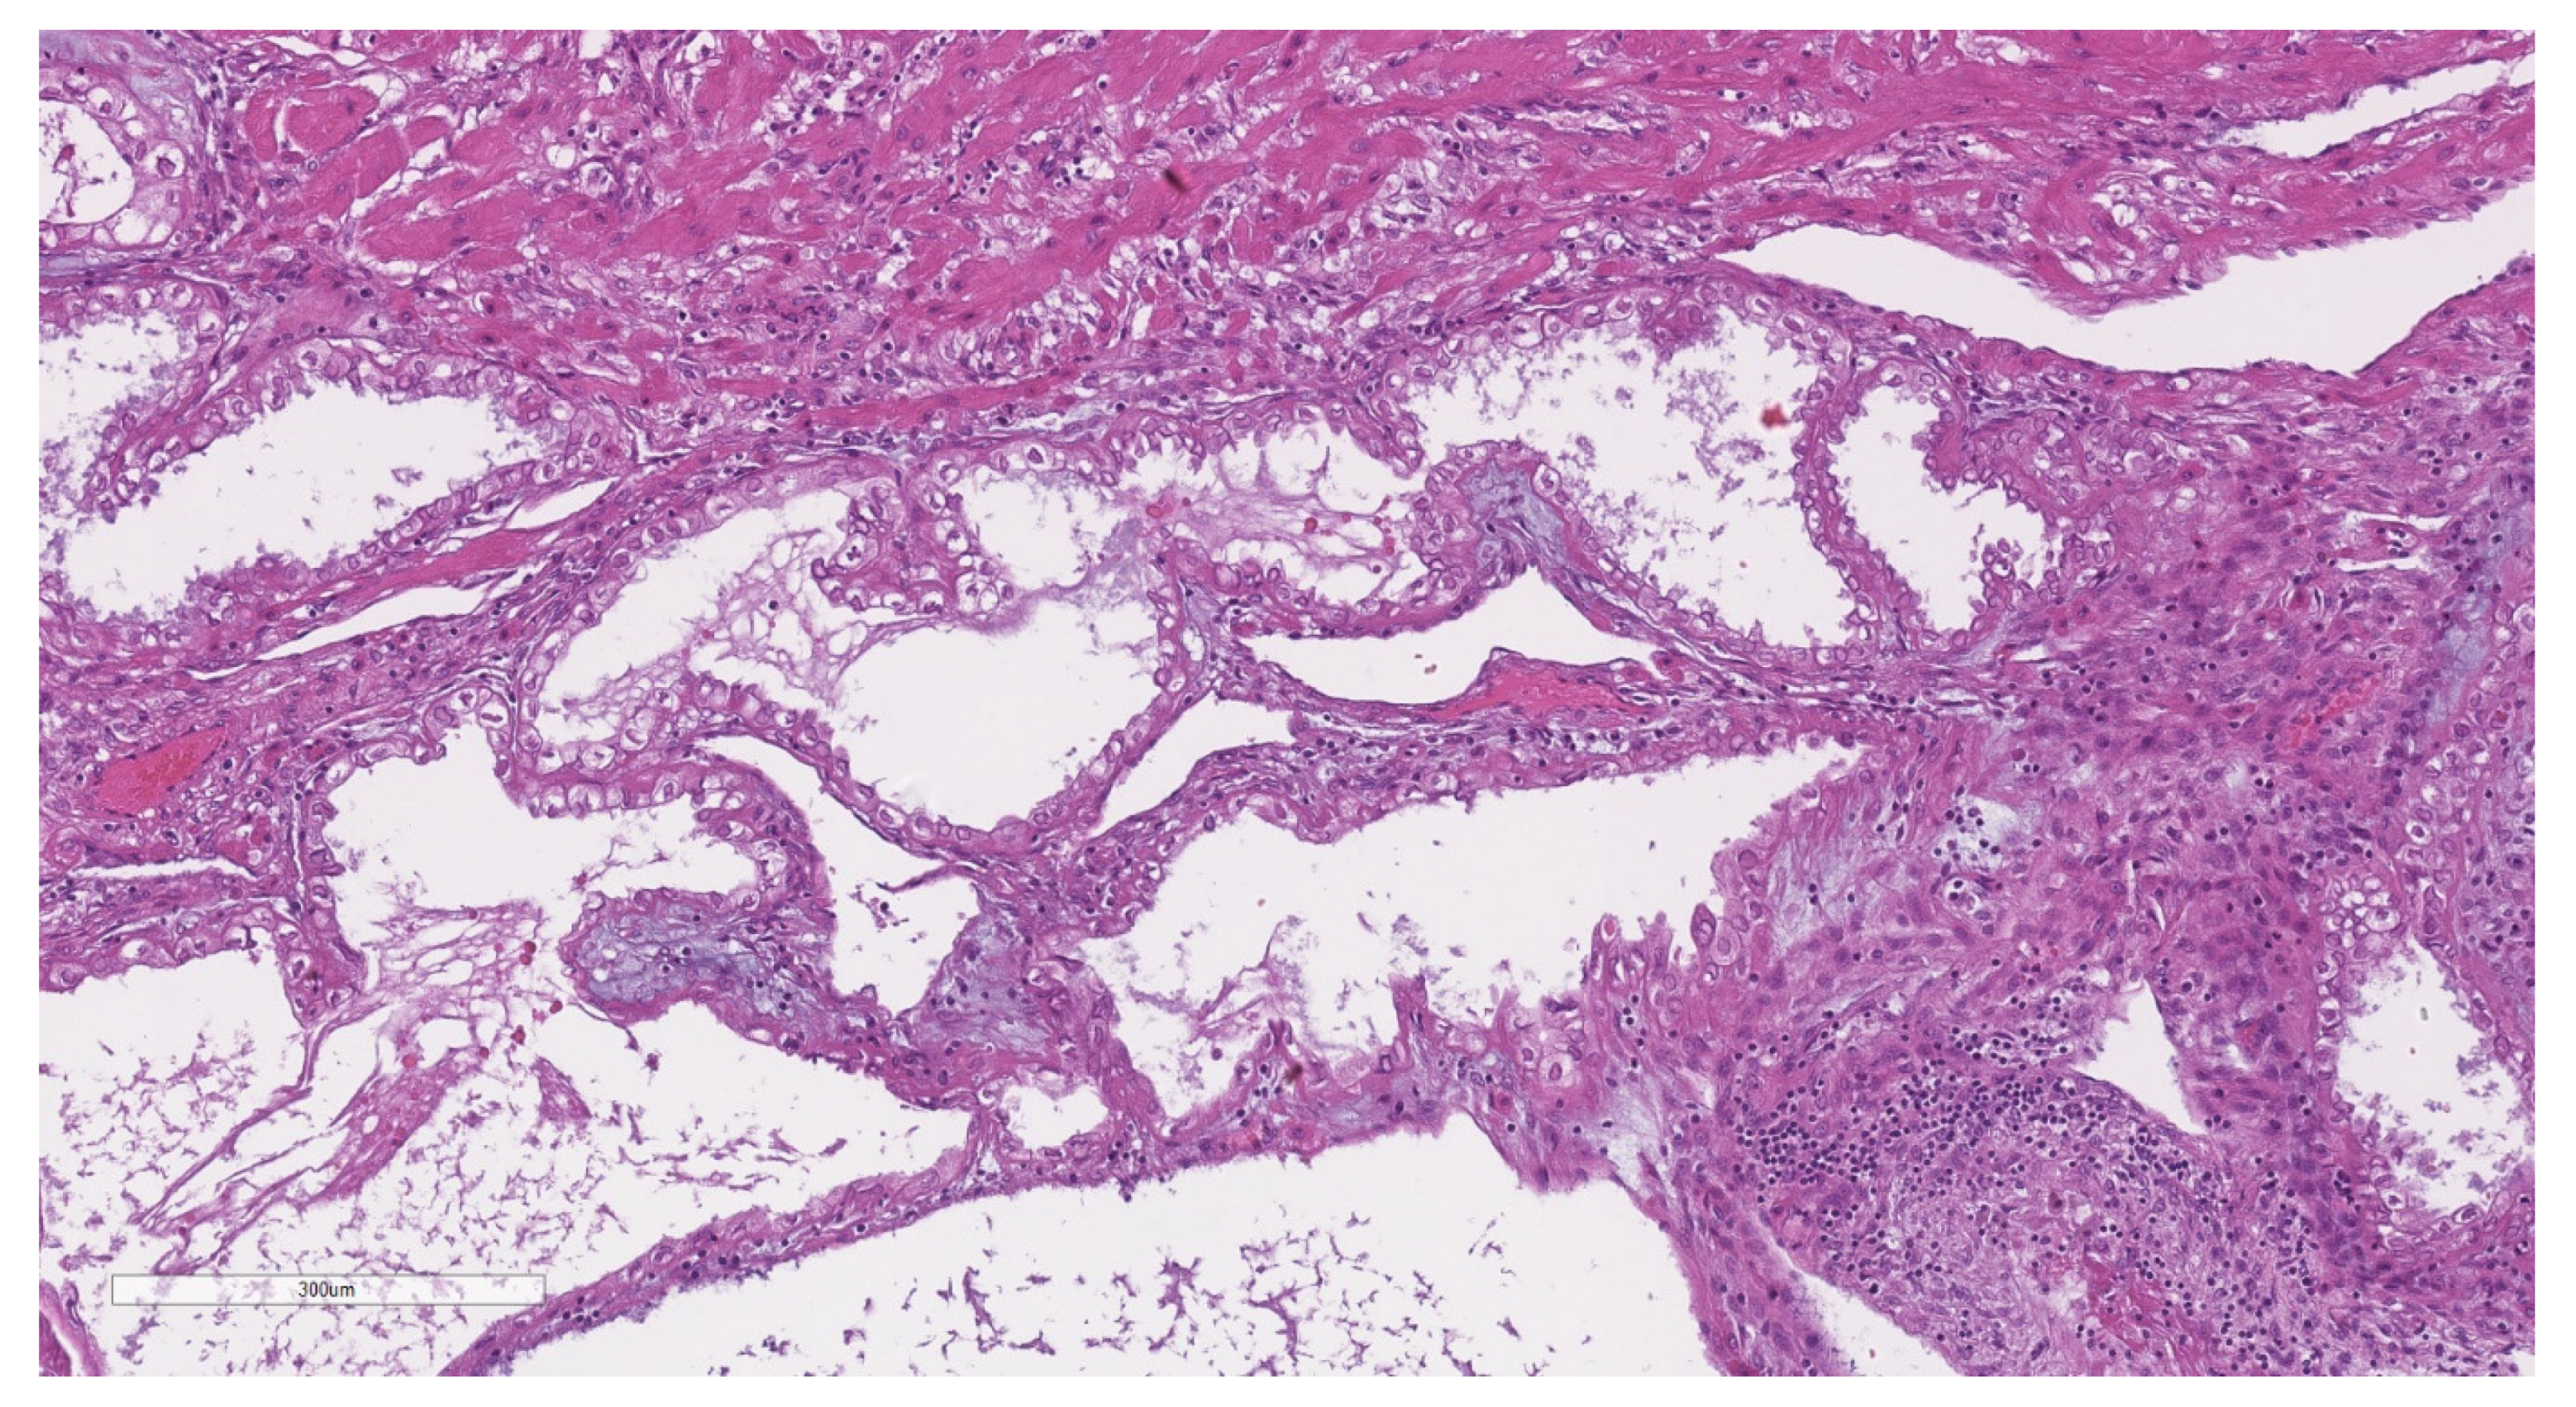

2.2. Histopathological Analysis